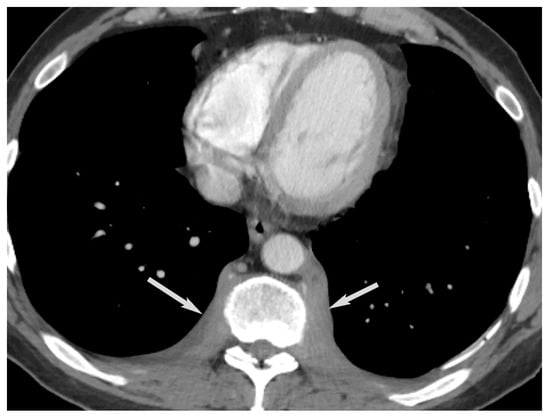

Paravertebral (Posterior) Compartment

11. Conclusions